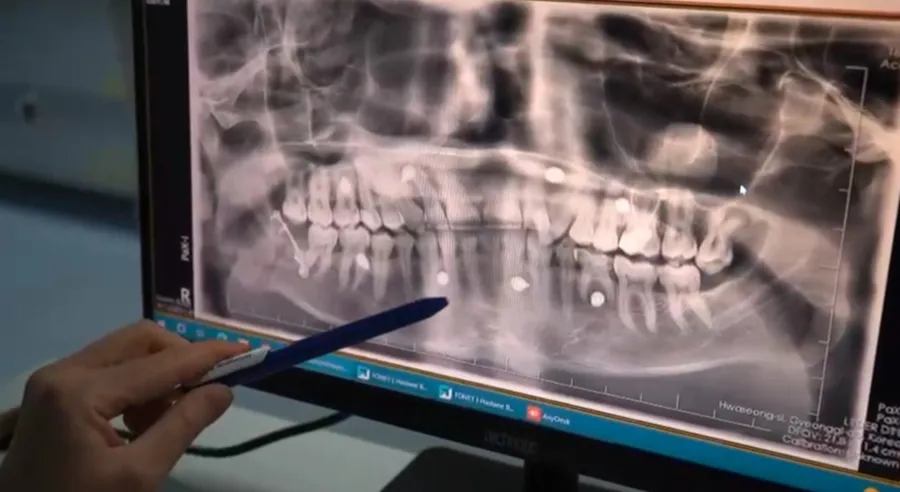

Batman’da yaklaşık 15 gün önce geçirdiği trafik kazasının ardından ağız açmada kısıtlılık, yüz bölgesinde şişlik ve ağrı ile dişlerde kapanış bozukluğu şikayetleriyle Batman Ağız ve Diş Sağlığı Hastanesi’ne başvuran Murat Aykut’ta, yapılan klinik ve radyolojik değerlendirmeler sonucunda sağ alt çene kırığı (mandibula) tespit edildi. Kırık kemik parçalarının hareketli olması nedeniyle hastaya açık cerrahi tedavi planlandı. Genel anestezi altında gerçekleştirilen ameliyatta ağız içinden yapılan kesiyle kırık hattına ulaşıldı, enfeksiyon riski taşıdığı değerlendirilen 20 yaş dişi çekildi. Ardından kemik segmentleri anatomik pozisyonuna getirildi ve plak-vida ile sabitlendi. Ameliyatın komplikasyonsuz tamamlandığı, hastanın aynı gün taburcu edilerek takibe alındığı bildirildi.

Ameliyatın güzel geçtiğini ifade eden Ağız Diş ve Çene Cerrahisi Uzmanı Doktor Ebru Baydan Çol: “Hastamız Murat bey bize ağız açmada kısıtlılık ve yüzünde şişlikle birlikte geldi. Hastanın hikayesinde travma sonrasında sağ alt çene 20 yaş bölgesinde kırık olduğunu tespit ettik. Yapılan muayeneler sonucunda hastanın açık ameliyatla bölgenin vida ve plakla yeniden eski yerinde konumlandırılması planlandı. Ameliyatımız güzel geçti. Herhangi bir komplikasyon gelişmedi. Hastamızı taburcu ettik. Batman'da bu ameliyat ilk defa yapıldı ve bundan sonra da düzenli olarak yapılmaya devam edecek" dedi.